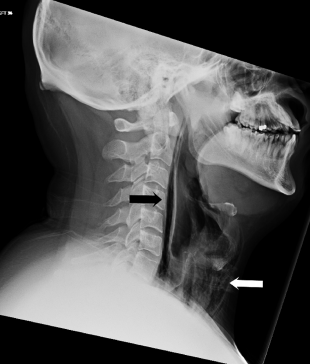

Именно это произошло с жителем Англии, который был помещен в больницу с жалобами на невозможность говорить и боли в горле. После неудачного чиханья в горле пациента появилась резь, а его шея вздулась, говорится в статье, описывающей необычный медицинский случай в журнале BMJ Case Reports. Во время обследования врачи обратили внимание на потрескивающий звук, возникающий при надавливании на обе стороны шеи, и вниз — до грудной клетки.

Этот симптом – крапитация, возникающая при попадании воздуха под кожу. Кроме того, при помощи компьютерной томографии был диагностирован пневмомедиастинум — скопление воздуха в клетчатке средостения. Врачи установили, что при попытке чихнуть у пациента произошел разрыв нижней части глотки, там, где она соединяется с пищеводом. В течение семи дней пациент питался через трубку и принимал антибиотики, после чего его состояние улучшилось.